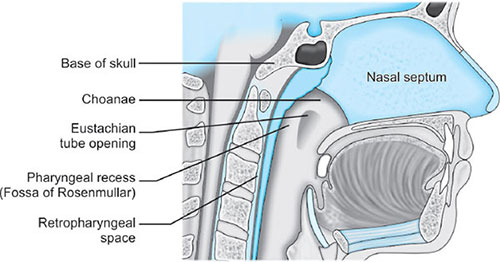

Lies parallel to vertebra, covered by anterior/longitudinal ligament and fascial layers beneath mucosa and constrictor muscles. The retropharyngeal space (between superficial buccopharyngeal fascia and prevertebral fascia) permits free movement of pharynx during deglutition. Retropharngeal abscesses may infiltrate to superior mediastinum through here.

- Nasopharynx: Extends from skull base to soft palate at caudal aspect of C1

Nasopharynx

The nose: The nose is divided into two nasal fossae which extend uo to 10 to 14 cm from the nostrils to the nasopharynx. The two fossae are divided by a cartilaginous septum. The nasal septum is composed of the perpendicular plate of the ethmoid bone descending from the cribriform plate, septal cartilage, and the vomer.

Disruption of the cribriform plate (due to facial trauma/head injury) may allow direct communication with the anterior fossa. Use of positive-pressure mask ventilation in such conditions may lead to the entry of bacteria or foreign material, causing meningitis or sepsis. Also there is a probability of nasal airways, nasotracheal tubes, and nasogastric tubes being introduced into the subarachnoid space.